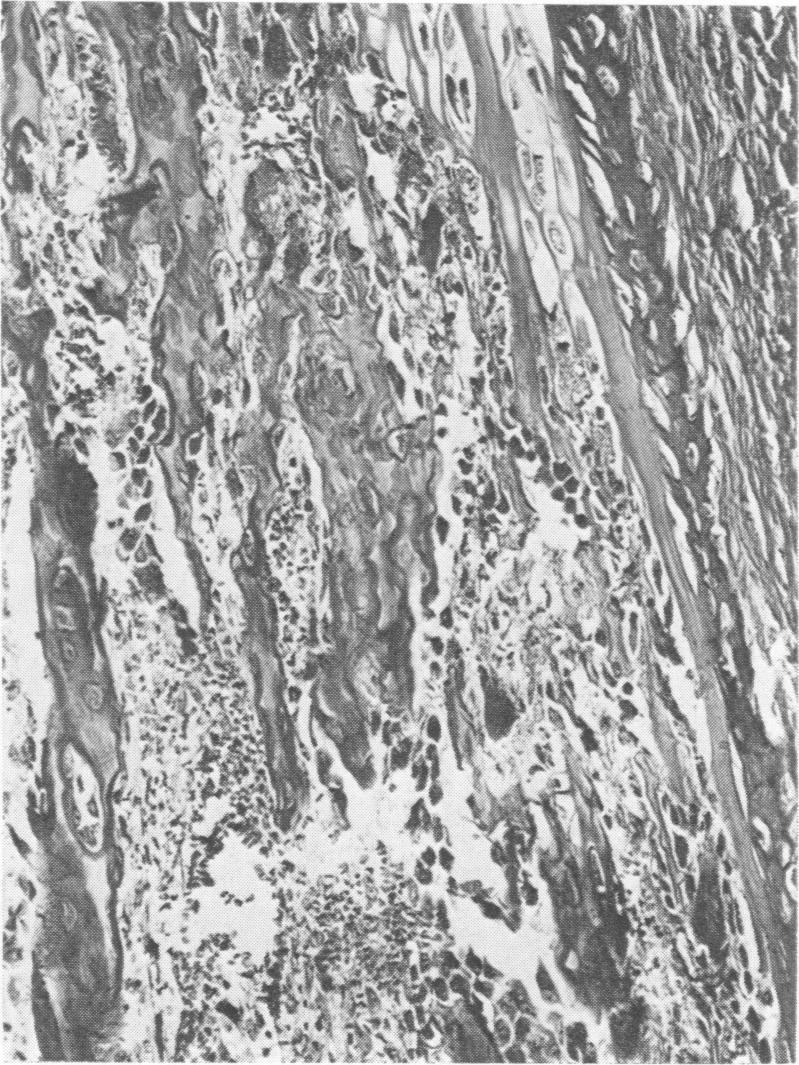

Disease in a large pig herd reared intensively and kept on sulfate-rich drinking water is described. It is the first report of diseased progeny of sows with high sulfate intake. Results of two surveys are presented, one for water with sulfate in excess of 2000 ppm and one for water with less than 1000 ppm. The management practices are described in detail. Disease of Survey I was manifested by high morbidity and mortality (50% of 600) in piglets, incoordination in piglets and some adult stock and osteopathy in piglets and weaners. In Survey II disease was less severe and restricted to piglets. Detailed histopathological studies revealed myelin deficiency in brain and spinal cord of sows and piglets, interferred endochondreal ossification of long bones of piglets and weaners, fatty changes of livers and interstitial nephritis in piglets and weaners. The changes in the nervous tissue were considered due to delayed fixation as tissue was only immersed in fixative and not perfused with it immediately after death. Similar changes have been described for pigs deficient in copper. Copper content of tissue and body fluids of pigs of this study were normal, as were the serum inorganic phosphate and total calcium levels. The bone changes observed have also been reported for rats given dextran sulfate injections, for pigs on experimental low-copper sulfate-enriched diet and for pigs reported low in copper and fed a diet supplemented with sulfide. The cause of the locomotor disturbance and mortality in piglets was not established.

描述了一个集约化饲养且饮用富含硫酸盐的饮用水的大型猪群中的疾病情况。这是关于高硫酸盐摄入量的母猪后代患病的首次报告。给出了两项调查结果,一项针对硫酸盐含量超过2000 ppm的水,另一项针对硫酸盐含量低于1000 ppm的水。详细描述了管理措施。调查I中的疾病表现为仔猪发病率和死亡率高(600头中有50%),仔猪和一些成年猪出现共济失调,仔猪和断奶仔猪出现骨病。调查II中的疾病较轻,仅局限于仔猪。详细的组织病理学研究显示,母猪和仔猪的脑和脊髓存在髓磷脂缺乏,仔猪和断奶仔猪的长骨软骨内骨化受到干扰,仔猪和断奶仔猪的肝脏出现脂肪变性和间质性肾炎。神经组织的变化被认为是由于固定延迟,因为组织只是浸泡在固定剂中,死后没有立即进行灌注固定。对于缺铜的猪也有类似变化的描述。本研究中猪的组织和体液中的铜含量正常,血清无机磷酸盐和总钙水平也正常。仔猪运动障碍和死亡的原因尚未确定。